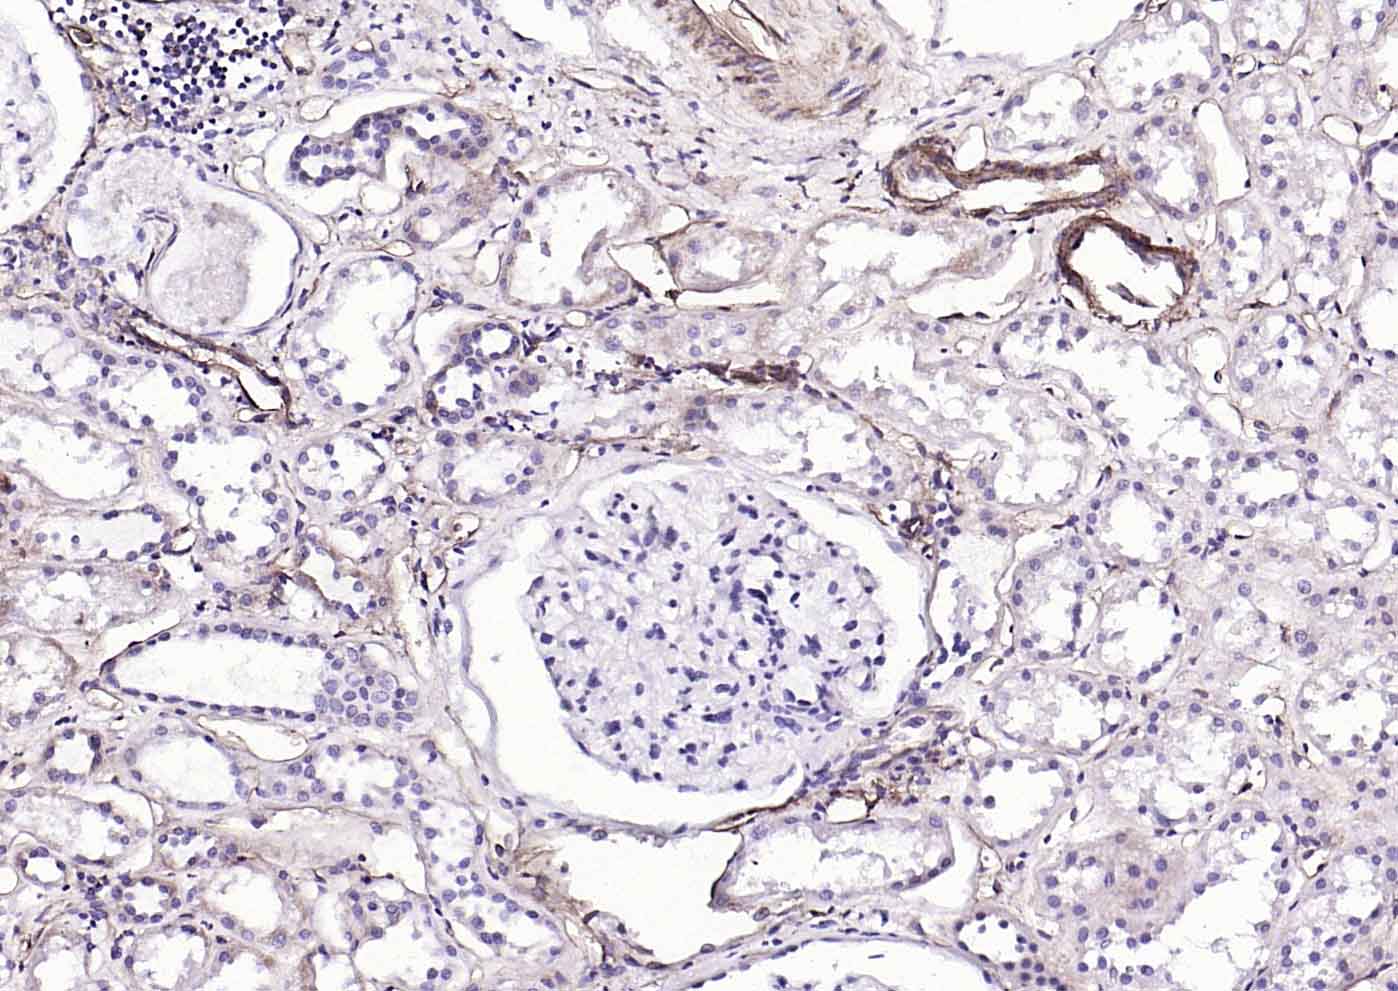

Paraformaldehyde-fixed, paraffin embedded (human kidney); Antigen retrieval by boiling in sodium citrate buffer (pH6.0) for 15min; Block endogenous peroxidase by 3% hydrogen peroxide for 20 minutes; Blocking buffer (normal goat serum) at 37°C for 30min; Incubation with (CD39/ENTPD1) Monoclonal Antibody, Unconjugated (bsm-54043R) at 1:200 overnight at 4°C, followed by operating according to SP Kit(Rabbit) (sp-0023) instructionsand DAB staining.